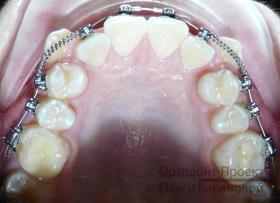

Брекеты Damon установлены:

![]() | ![]() |

На текущем этапе ортодонтического лечения использование брекетов сфокусировано на расширении зубного ряда в области второго и четвертого зубов, при этом на системе установлены специальные пружины.

Через пять месяцев начинается новый этап — возвращение клыков на их естественное место в зубном ряду. Вторая дуга обеспечивает стабильное положение передних резцов.